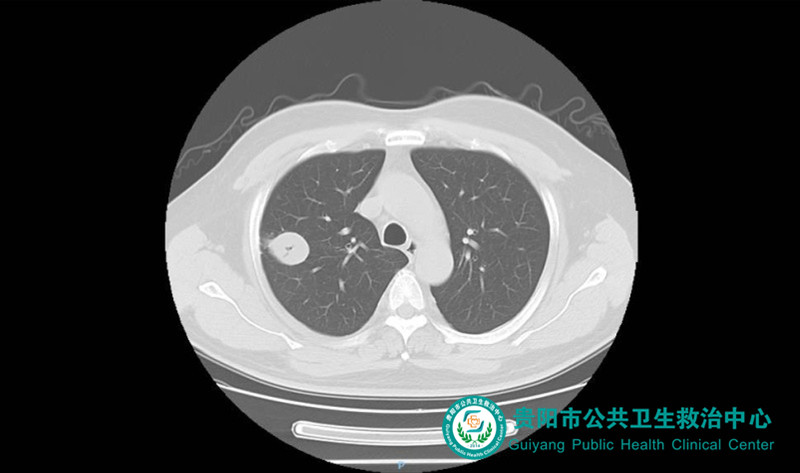

患者因“咳嗽、咳痰1月余”入院。入院時胸部CT提示:右上肺類圓形腫塊,考慮肺結核球。入院后積極完善相關檢查,排除手術禁忌癥后由我院胸外科和麻醉科聯(lián)合為患者實施了目前國內(nèi)領先的麻醉、手術方式——非氣管內(nèi)插管全身麻醉下單孔胸腔鏡手術。

肺腫物胸部CT表現(xiàn)1

肺腫物胸部CT表現(xiàn)2